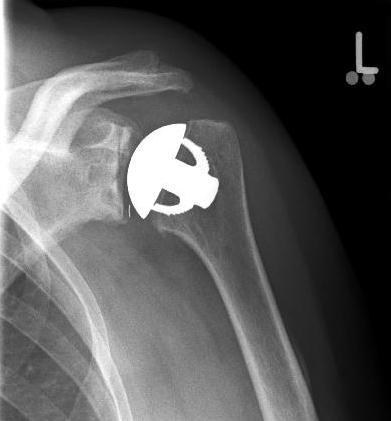

left: X-ray image of an omarthrosis

right: X-ray of a healthy shoulder joint